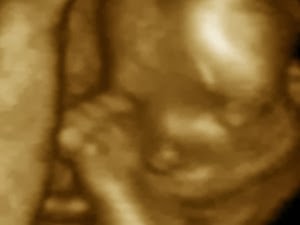

Los gemelos se acarician en la panza de mamá

Científicos italianos de las universidades de Turin y Parma han descubierto que, con sólo 18 semanas de gestación, los bebés ya quieren socializarse dentro del vientre materno. A esta conclusión han llegado tras estudiar los movimientos de cinco parejas de fetos gemelos con ultrasonografía, una técnica dinámica tridimensional. Los detalles se publican en la revista PLoS ONE.

En las primeras grabaciones de 20 minutos de duración, tomadas a las 14 semanas de embarazo, observaron que los bebés se tocaban un poco entre sí, pero también se tocaban a sí mismos (los ojos y la boca principalmente), además de acariciar la pared uterina. Cuatro semanas más tarde, el 30% de los movimientos iban dirigidos a su hermano, muchos en forma de lo que podría interpretarse como caricias en la cabeza, y se prolongaban durante más tiempo. “El perfeccionamiento de los movimientos dirigidos al contacto con el hermano gemelo no es accidental y empieza en la semana 14 de gestación” concluyen los autores, que añaden que los humanos estamos “diseñados para ser sociales” y que nuestro interés por la comunicación se desarrolla de modo natural a medida que elsistema neuronal madura.